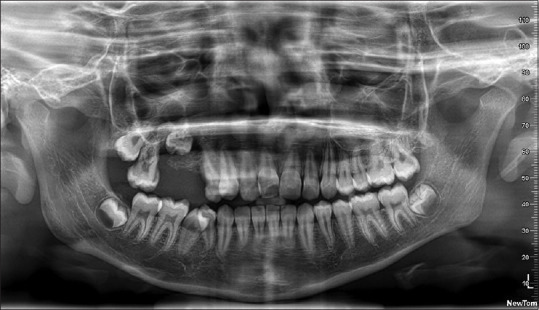

Patient concerns: A 14-year-old male patient reported with a chief complaint of swelling in the right upper back tooth region for four months.

Diagnosis: Incisional biopsy of the lesion shows numerous dilated and thin-walled blood vessels and focal areas of chronic inflammatory cell infiltrate beneath the epithelium suggestive of angiofibroma.